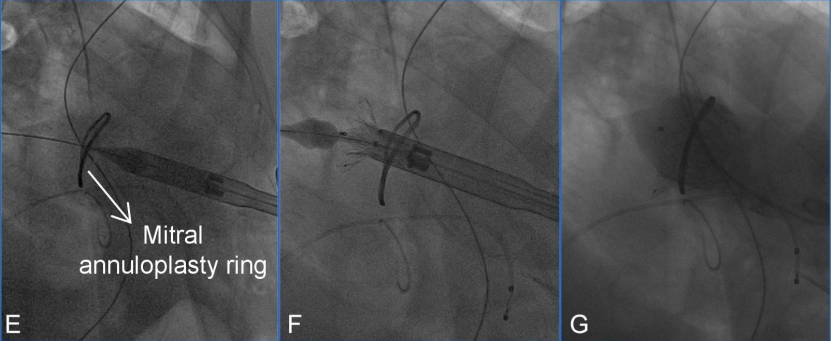

4. The 33 mm Mi-thos biological valve was assembled with the delivery system in vitro, and then a puncture was completed at the apex, followed by the insertion of a 6F sheath, which was then advanced through the 6F pig-tail catheter and J-tip 0.035 inch guidewire across the surgically repaired mitral valve annulus into the left atrium. Subsequently, a 260 cm Lunderquist super stiff guidewire (Cook Medical, Bloomington, Indiana, USA) was exchanged.

5. The delivery system was then advanced retrogradely through the apical approach across the mitral valve repair ring into the left atrium along the guidewire. By retracting the outer sheath of the delivery system, the atrial skirt designed to fit the D-shaped mitral valve annulus was precisely covered over the original annulus and repair ring under the guidance of TEE and angiography, while the ventricular portion of the valve remained partially retained in the sheath.

Discussion on the Structure Literature of Xijing|3D Printing-Assisted Innovative System for Transcatheter Mitral Valve "Valve-in-Ring" Replacement SurgeryFigure E-G: Main surgical steps of transcatheter mitral “valve-in-ring” replacement surgery. (E) The delivery system was successfully delivered via the apical approach. (F) The biological valve was released. (G) Angiography indicated appropriate valve positioning.Discussion on the Structure Literature of Xijing|3D Printing-Assisted Innovative System for Transcatheter Mitral Valve "Valve-in-Ring" Replacement Surgery

6. After confirming the position and alignment of the Mi-thos valve, the delivery system was slowly retracted to accurately position it on the annulus. Subsequently, the ventricular portion of the valve was released under rapid pacing at 140 beats per minute, and it was firmly anchored in the native mitral valve position using its built-in fixation barbs.

7. Intraoperative left ventricular angiography immediately showed that the Mi-thos biological valve was well positioned and shaped, with no intravalvular regurgitation, paravalvular leak (PVL), or left ventricular outflow tract obstruction (LVOTO) observed (the new left ventricular outflow tract area was 374.6 cm²); TEE further assessed the valve position and function, showing an average transvalvular pressure gradient of 3 mmHg.